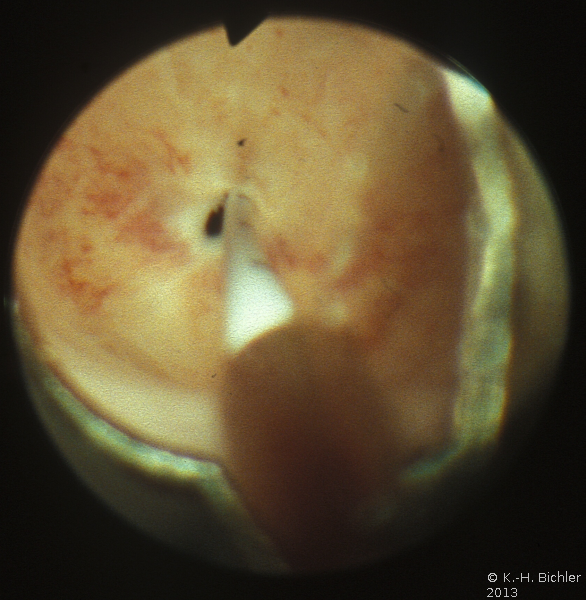

Die Abbildung zeigt das Verfahren der endoskopischen inneren Schlitzung bei Harnröhrenobstruktion (Abbildung 13).